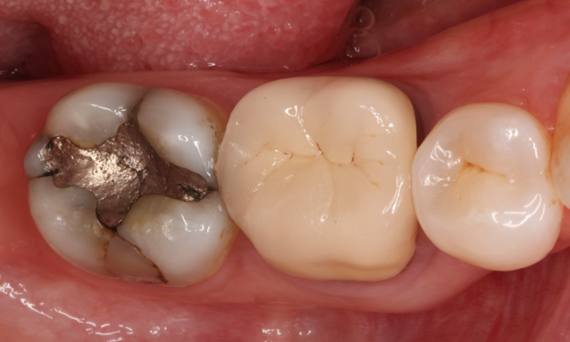

Lower second molar chairside restoration

A partial CEREC Tessera crown

A lower second molar with sensitivity presented with cracks as well as an extensive Class I composite restoration on the buccal surface. According to the minimally invasive concept a CAD/CAM partial crown was planned, fabricated and bonded using CEREC Tessera in a single visit.

Before: Failed amalgam restoration needing replacement. Patient complaining of sensitivity and tooth presenting multiple cracks.

After: Chairside CAD/CAM partial crown restoration fabricated with CEREC Tessera Advanced Lithium-Disilicate glass ceramic.